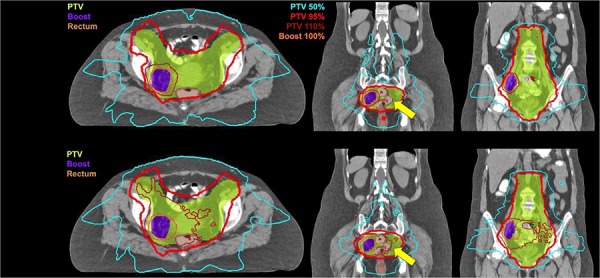

Dosimetric parameters collected for each volume are listed in Table 2. There was no significant change in nodal boost volume between the initial and boost simulation scans . Comparable pelvic target volume coverage (V90% and V95%) was achieved with sequential boost and SIB plans, while hot spots (V110% and V115%) were significantly reduced using SIB. Coverage of boost target volumes was similar in both treatment groups, with little dose heterogeneity (Fig. 1).

Figure 1.

Dose distribution in axial and two coronal views obtained by sIMRT and SIB IMRT plans. SIB provides equally conformal (CI95%) and more homogenous doses (see V95%, V110%) to target volumes (colorwash) while sparing OAR (see yellow arrow).